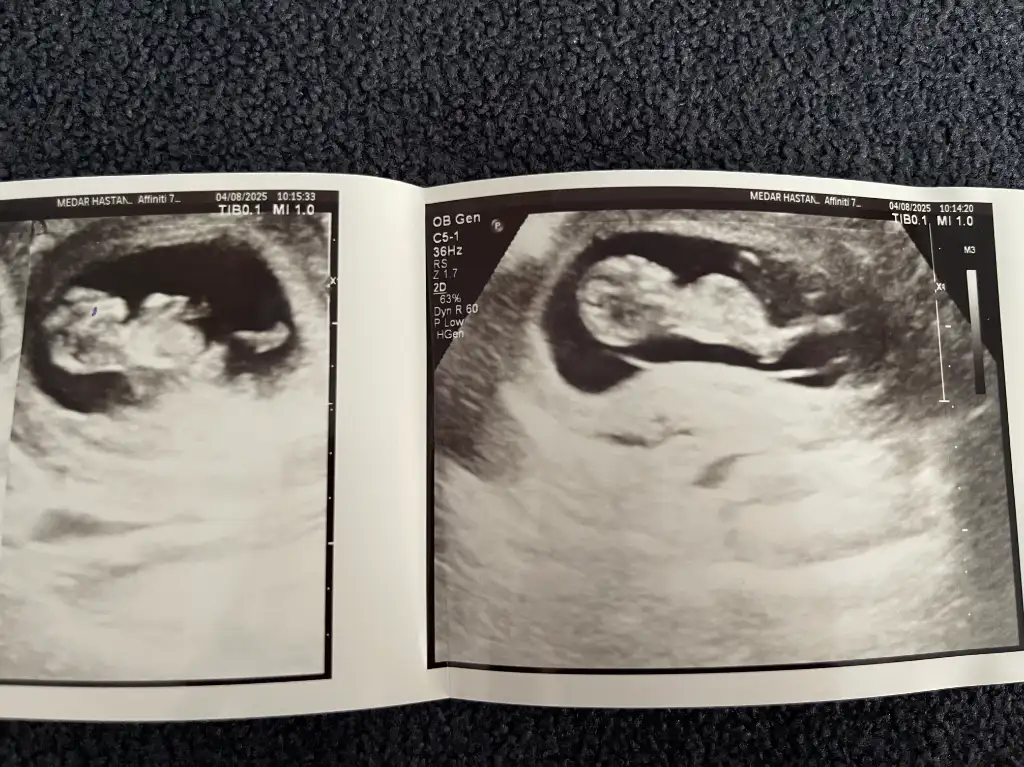

Erkek bencemerhaba 11+6 haftalık ilk ve son karından ultrason fotoğraflarını ekledim rica etsem bakabilir misiniz

Oğlumun kesesıne benzıyor..Sağlıkla gelsinmerhaba 11+6 haftalık ilk ve son karından ultrason fotoğraflarını ekledim rica etsem bakabilir misiniz

merhabalar evet erkekmiş teşekkür ederim insallahOğlumun kesesıne benzıyor..Sağlıkla gelsin